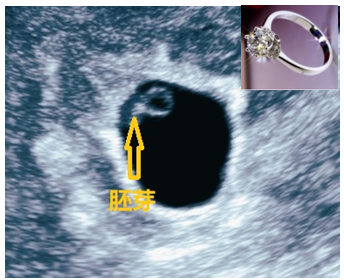

孕7-8周,TA终于刷出存在感了(图4)。在之前的卵黄囊边上,我们终于看到了点状的TA。两者结合起来就像钻戒一样光彩夺目。实时超声下“戒指”上的“钻石”一闪一闪,正是TA快速搏动的心管。至此,宝妈应该可以放心了:小天使终于找到了正确的位置且存活下来。

图4 超声显示:宫内早孕